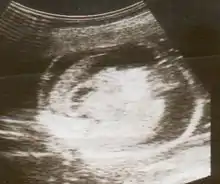

An ultrasound showing a fetus with hydrops fetalis

Hydrops fetalis can be diagnosed and monitored by ultrasound scans.[1] An official diagnosis is made by identifying excess serous fluid in at least one space (ascites, pleural effusion, of pericardial effusion) accompanied by skin edema (greater than 5 mm thick). A diagnosis can also be made by identifying excess serous fluid in two potential spaces without accompanying edema. Prenatal ultrasound scanning enables early recognition of hydrops fetalis and has been enhanced with the introduction of MCA Doppler.[7]